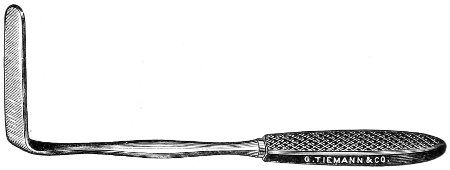

Fig. 4.—Double tenaculum.

The examination of the uterus and other pelvic structures is often facilitated by dragging the uterus downward with a tenaculum while the vaginal or the bimanual examination is being made. Sensation in the cervix is so slight that little or no pain is experienced in this procedure. The anterior or posterior lip of the cervix is caught with the single or the double tenaculum (Fig. 4), guided along the vaginal finger or introduced through the speculum, and the uterus is drawn down by an assistant in case the bimanual examination is being made, or by the external hand of the examiner in case a simple vaginal examination is made. When this is done the utero-sacral ligaments are made tense, and can be felt like two cords extending from the sides of the cervix outward and backward to the pelvic wall. The posterior surface of the uterus can be palpated often as high up as the fundus. The method is especially useful when the examination is made by the rectum, and in this way the whole posterior surface and the fundus of the uterus may be palpated (Fig. 5).

Fig. 5.—Bimanual examination with one finger in the rectum. The uterus is drawn down with the double tenaculum.